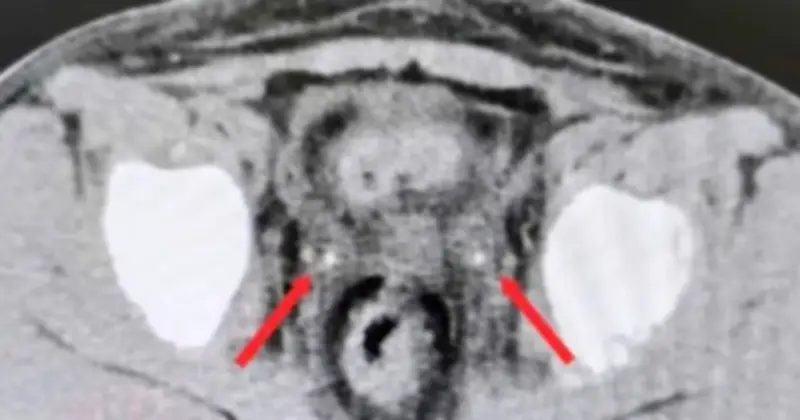

Khi được chuyển đến Bệnh viện Nhi đồng 2, bệnh nhi trong tình trạng không có nước tiểu, và siêu âm không phát hiện thấy nước tiểu trong bàng quang. Kết quả chụp CT bụng không cản quang đã ghi nhận thận ứ nước hai bên, niệu quản giãn và sỏi kẹt ở đoạn cuối hai bên, với kích thước 3x7mm bên phải và 3x20mm bên trái. Ngay lập tức, bệnh nhi được tiến hành mổ cấp cứu trong đêm, với phương pháp nội soi bàng quang để đặt ống thông JJ ngược dòng hai bên.